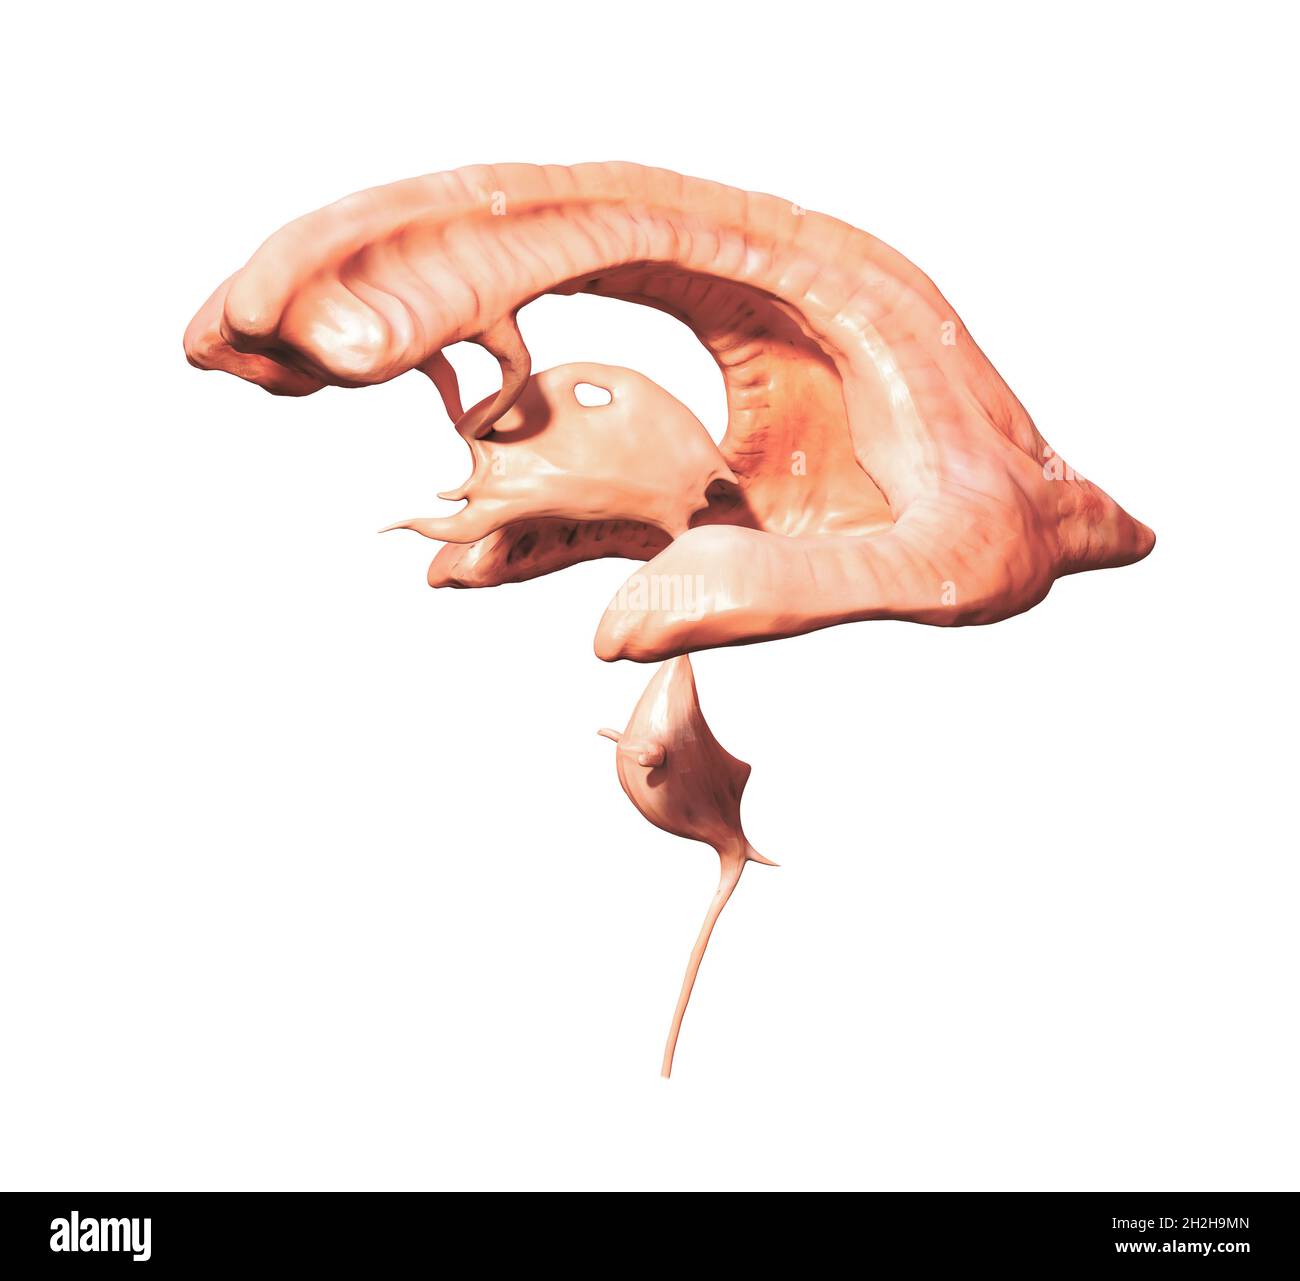

RMG155NT–Illustration einer sagittalen Abschnitt der dritten und vierten Ventrikel des Gehirns. Die Ventrikel enthalten Liquor cerebrospinalis, die das Gehirn dämpft. Dies ist eine historische Darstellung aus den 1890er Jahren.

RMG155NW–Verbesserte Darstellung der sagittalen Abschnitt der dritten und vierten Ventrikel des Gehirns Farbe. Die Ventrikel enthalten Liquor cerebrospinalis, die das Gehirn dämpft. Dies ist eine historische Darstellung aus den 1890er Jahren. (Abb. BS4911)